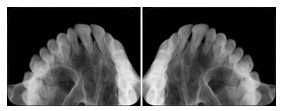

2. A patient requests cosmetic surgery to enhance their facial appearance. The case requires consultation between an orthodontist in New York and an oral surgeon in California. The cephalometric series of 2D projections constructed from the volumetric CT data that is used for the discussion is arranged by a Structured Display for transfer between the two practitioners.

Cephalometric Series Structured Display

Figure OO-2. Cephalometric Series Structured Display